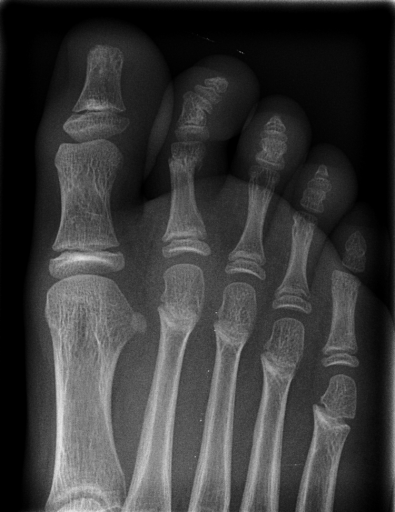

In this series of experiments, we randomly selected three categories from IRMA dataset (namely, breast, foot and lung), and for each category we choose 5 random images from that class (Figures 5, 6 and 7 show these images). When we find “4 out of 180” (4/180) and “8 out of 180” (8/180) projections via micro-DE (tasks that cannot be performed via brute-force), then the question is what can we say about the reconstruction error, in terms of correlation between original and reconstructed images, when we compare evolutionary approximation with the case that we can manage via exhaustive search, namely “4 out of 16” (4/16)? Can micro-DE reach at least the same correlation (similarity) as the brute-force case in lower dimensions? If yes, we may have more confidence in using micro-DE in practice where we cannot apply brute force for benchmarking or direct use, especially for higher dimensions (i.e., the number of projections).

For finding optimal projections based on micro-DE (4 out of 180), we set the parameters of micro-DE to be NFC, , , , and we run each experiment 30 times. For optimal projections based on micro-DE (8 out of 180), we set NFC, , , , and we run each experiment 30 times. The results are presented in Tables 2, 3 and 4. In all cases, micro-DE (MDE) with 4/180 reaches the same correlations as brute force (BF) for 4/16. Of course, MDE finds different projections as it is searching the entire search space of . However, that the same level of reconstruction accuracy can be achieved establishes the reliability of MDE as a practical solution that may even produce a higher-level of uniqueness for Radon barcodes as 4 projections are selected among all 180 angles (the increased uniqueness needs to be verified by applying the Radon barcodes for image retrieval). On the other hand, MDE for 8/180 clearly increases the correlation with statistical significance. This is very encouraging as we can generate more expressive Radon barcodes using a higher number of projections.

| image | BF (4/16) | MDE (4/180) | MDE (8/180) | |||

|---|---|---|---|---|---|---|

| f1 | [34,67,112,157] | 0.79 | [30,80,110,150] | 0.80 | [80,160,30,130,30,100,140,60] | 0.85 |

| f2 | [79,101,135,169] | 0.73 | [80,110,140,170] | 0.73 | [70,20,160,0,120,80,130,100] | 0.80 |

| f3 | [11,56,112,158] | 0.64 | [20,60,100,170] | 0.65 | [40,130,160,70,10,170,110,60] | 0.70 |

| f4 | [11,79,101,169] | 0.77 | [0,30,80,100] | 0.77 | [20,180,50,60,80,110,170,120] | 0.84 |

| f5 | [22,67,112,157] | 0.85 | [80,30,120,160] | 0.86 | [120,60,80,10,150,100,170,40] | 0.89 |